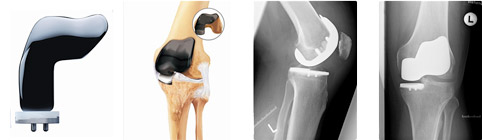

PROTESI MONOCOMPARTIMENTALI

- Il ginocchio è diviso in tre compartimenti principali: il compartimento mediale (la parte interna del ginocchio), il compartimento laterale (la parte esterna) e il compartimento femoro-rotuleo (la parte anteriore del ginocchio tra il femore e la rotula).

In casi selezionati, pazienti con un’artrosi localizzata ad un solo compartimento del ginocchio (generalmente quello interno o mediale) possono essere candidati per una protesi monocompartimentale in cui solo la porzione del ginocchio danneggiata viene sostituita dalle componenti protesiche.

I vantaggi di questo tipo di protesi sono rappresentati da una minor invasività, dalla preservazione dei legamenti e quindi di una più fisiologica biomeccanica del ginocchio che si traduce in una ripresa più veloce e in un recupero migliore della funzionalità.

Sono state recentemente introdotte anche protesi cosiddette bicompartimentali (Duece) che permettono la sostituzione sia del compartimento femoro-rotuleo che di quello mediale.